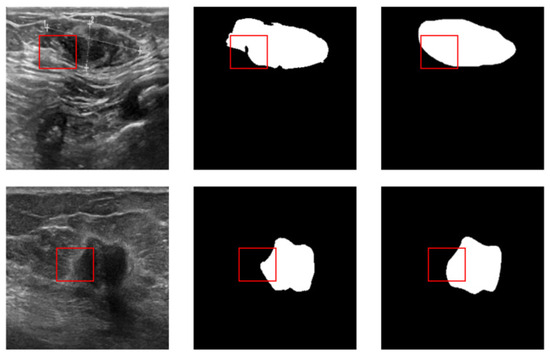

4.1. Dataset and Preprocessing